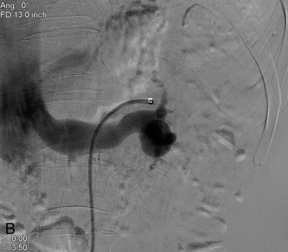

АНЕВРИЗМА ПОЧЕЧНЫХ АРТЕРИЙ

Диагноз аневризмы или псевдоаневризмы почечной артерии чаще всего ставится с помощью КТ или МРТ. Однако есть результаты допплерографии, которые можно увидеть при этой аномалии. Он может выглядеть как сосудистая структура веретенообразной, эксцентрической и мешотчатой формы. РАА обычно возникает из точки ветвления внутри артерии. При цветном допплеровском исследовании могут наблюдаться круговые потоки крови, напоминающие «инь-ян» ( рис. 9-18 ). Часть аневризмы может быть тромбирована. Для RAA характерно наличие периферических кальцификаций, которые могут ограничивать сонографическую оценку центрального кровотока.

РИСУНОК 9-18. Аневризма почечной артерии. (A) На разделенном изображении показана безэховая круглая структура в оттенках серого с потоком в цветном допплеровском режиме. Круговой поток на цветном допплеровском изображении (стрелки), называемый знаком «инь-ян», можно увидеть при аневризме или псевдоаневризме. (Б) При ангиографии подтверждается типичная круглая сосудистая структура аневризмы.